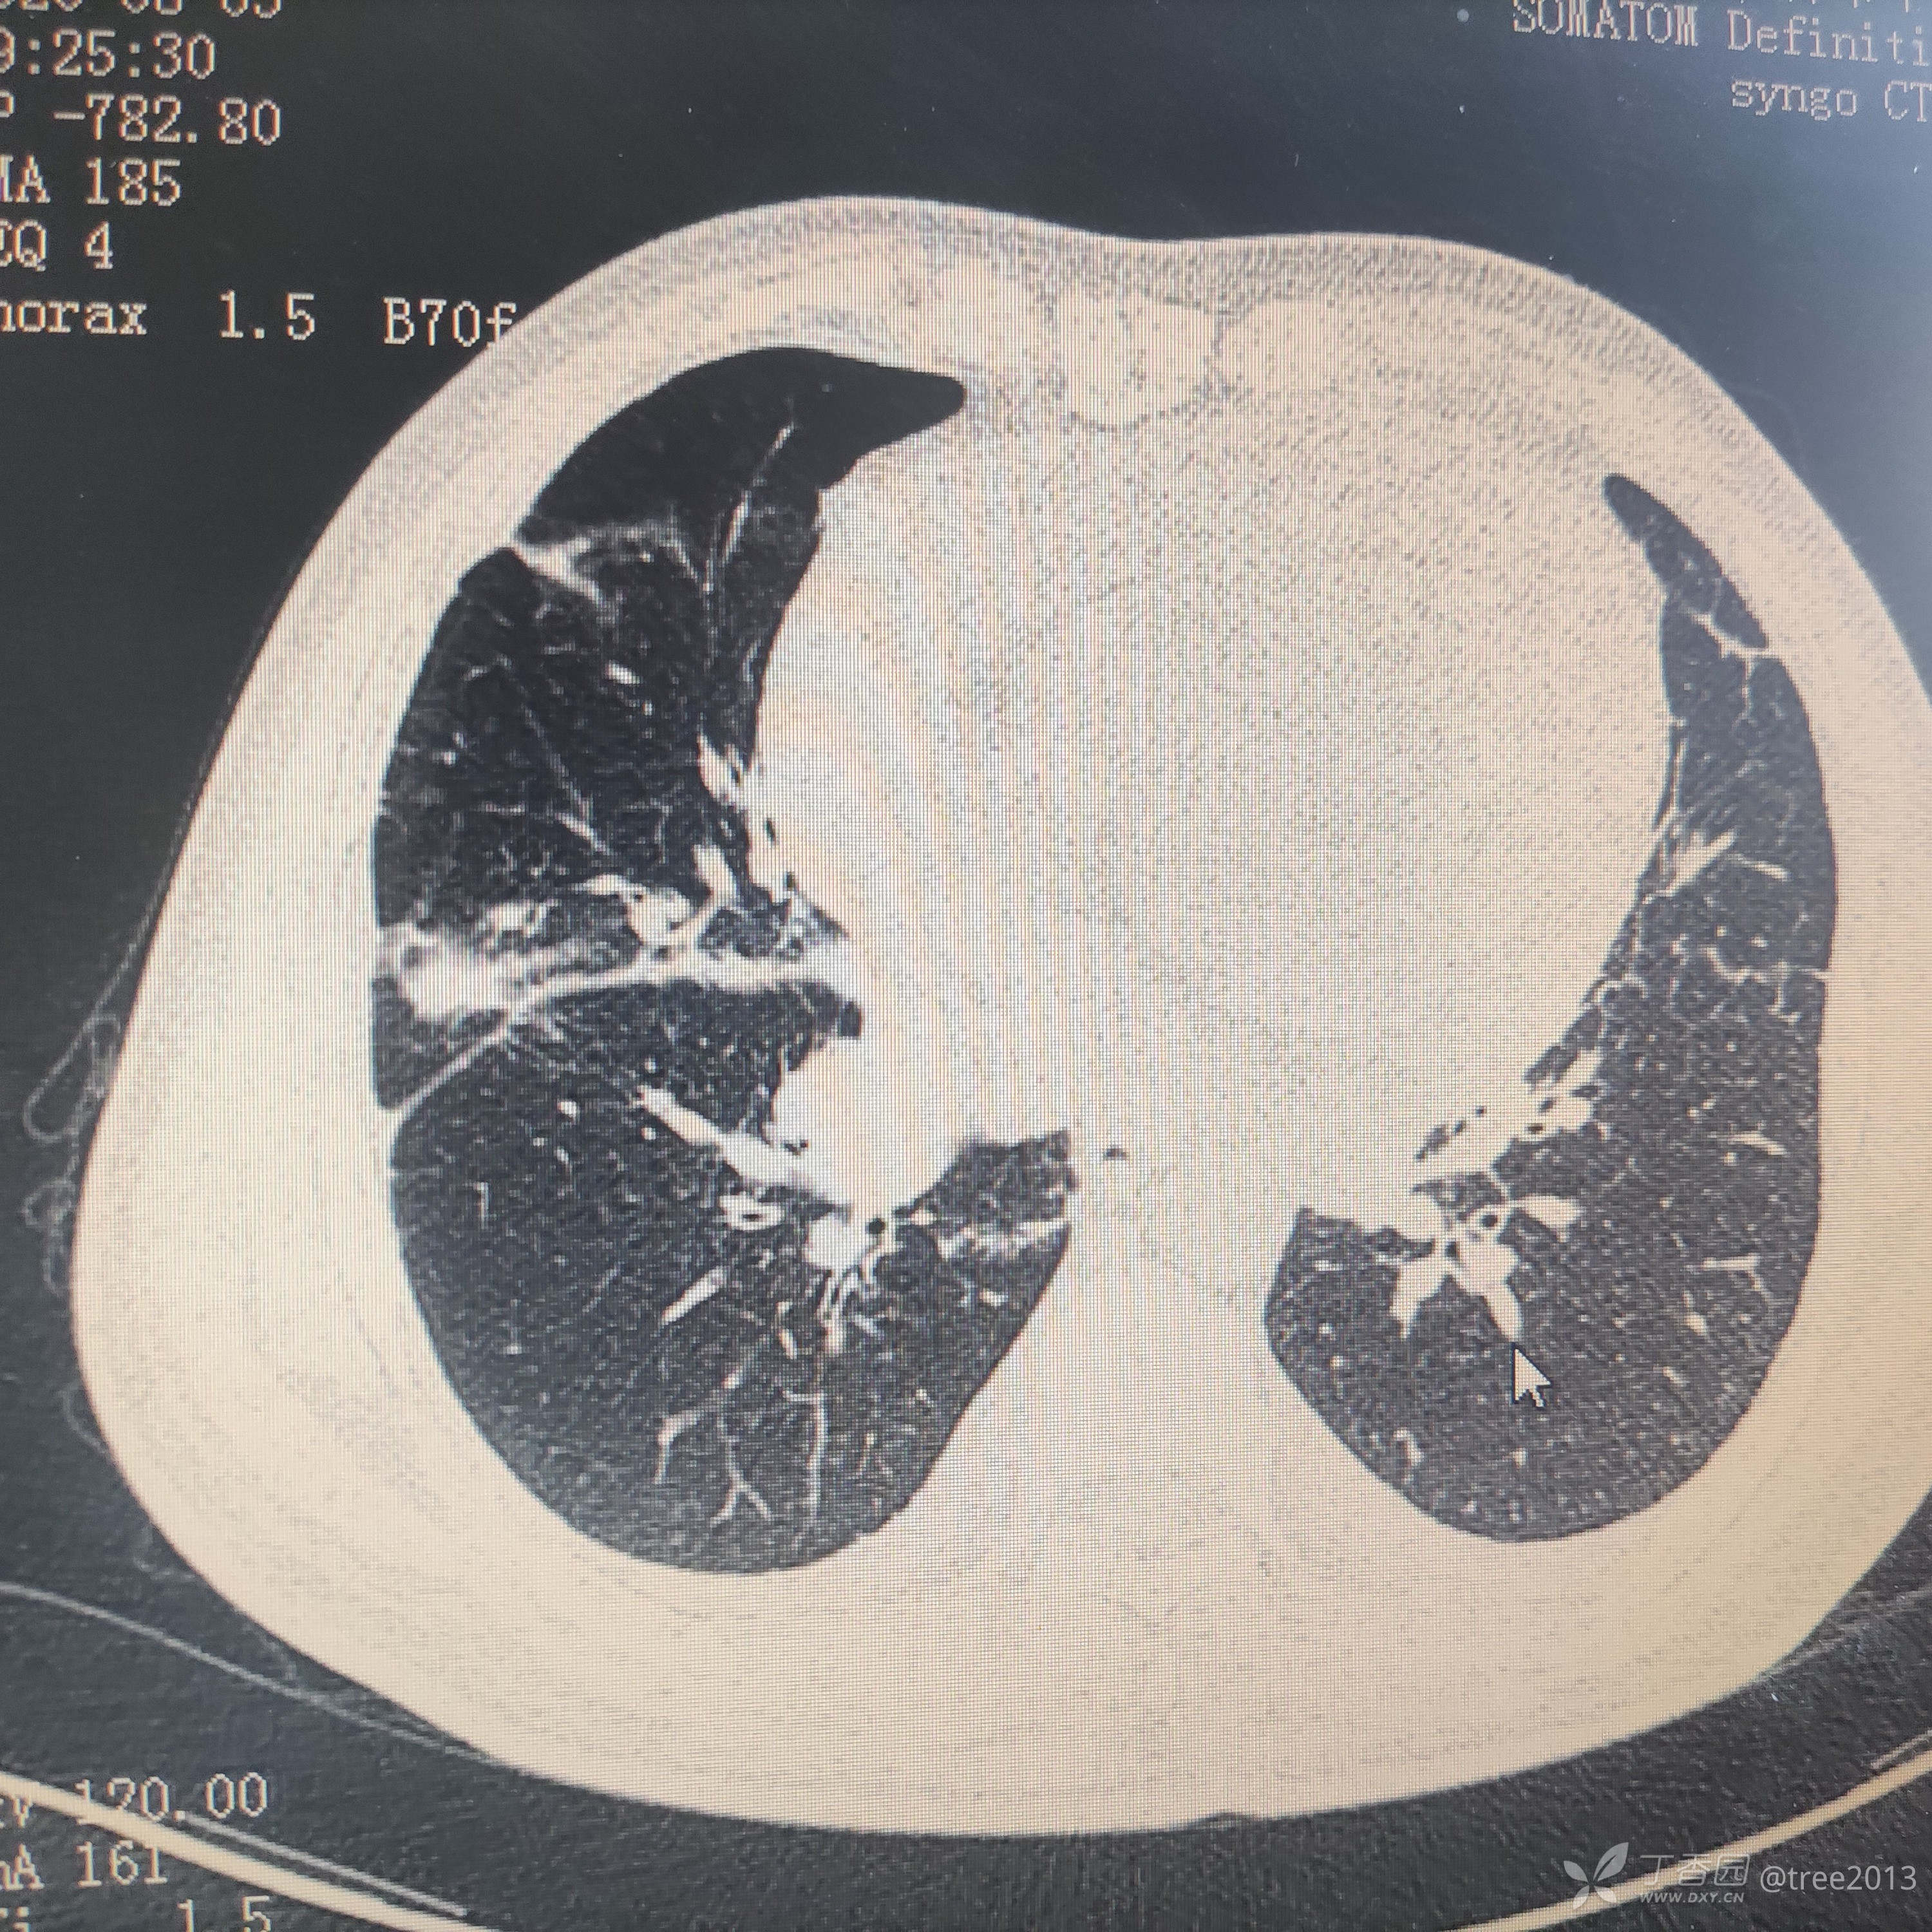

胸部CT:

诊断:肺部恶性肿瘤伴多大转移 心包积液 胸腔积液